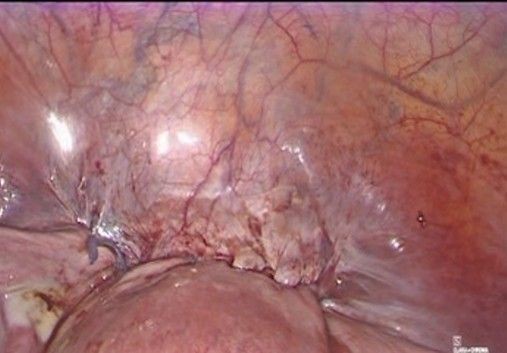

- Final review and closure (Figure 12-13): The absence of bleeding is verified along the dissection path and around uterine vessels, the vesicouterine peritoneum is repositioned over the dissected area, covering the tape knot, and trocars are removed under direct vision and the cavity is deflated.

Figure 12: Repositioning of the vesicouterine peritoneum

Figure 13: final aspect before removal of the trocars